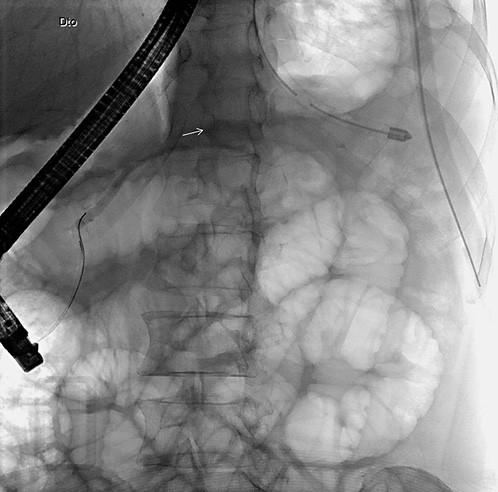

In light of these findings, a thoracoabdominal computed tomography (CT) was performed, revealing a homogeneous and fluid peripancreatic collection with a well-defined enhancing rim, close to the upper border of the pancreatic body, with a maximum diameter of 48 mm, which exhibited two fistulous tracts: one to-wards the spleen and another to the diaphragm (Fig. 2). No abnor-malities were found on the pancreatic parenchyma, gallbladder, and bile ducts and there were no abdominopelvic adenopathies.

Fig. 2 Thoracoabdominal computed tomography showing a peripancreatic collection with a fistulous tract towards the spleen (right image, white arrow) and another to the diaphragm (left image, white arrow).